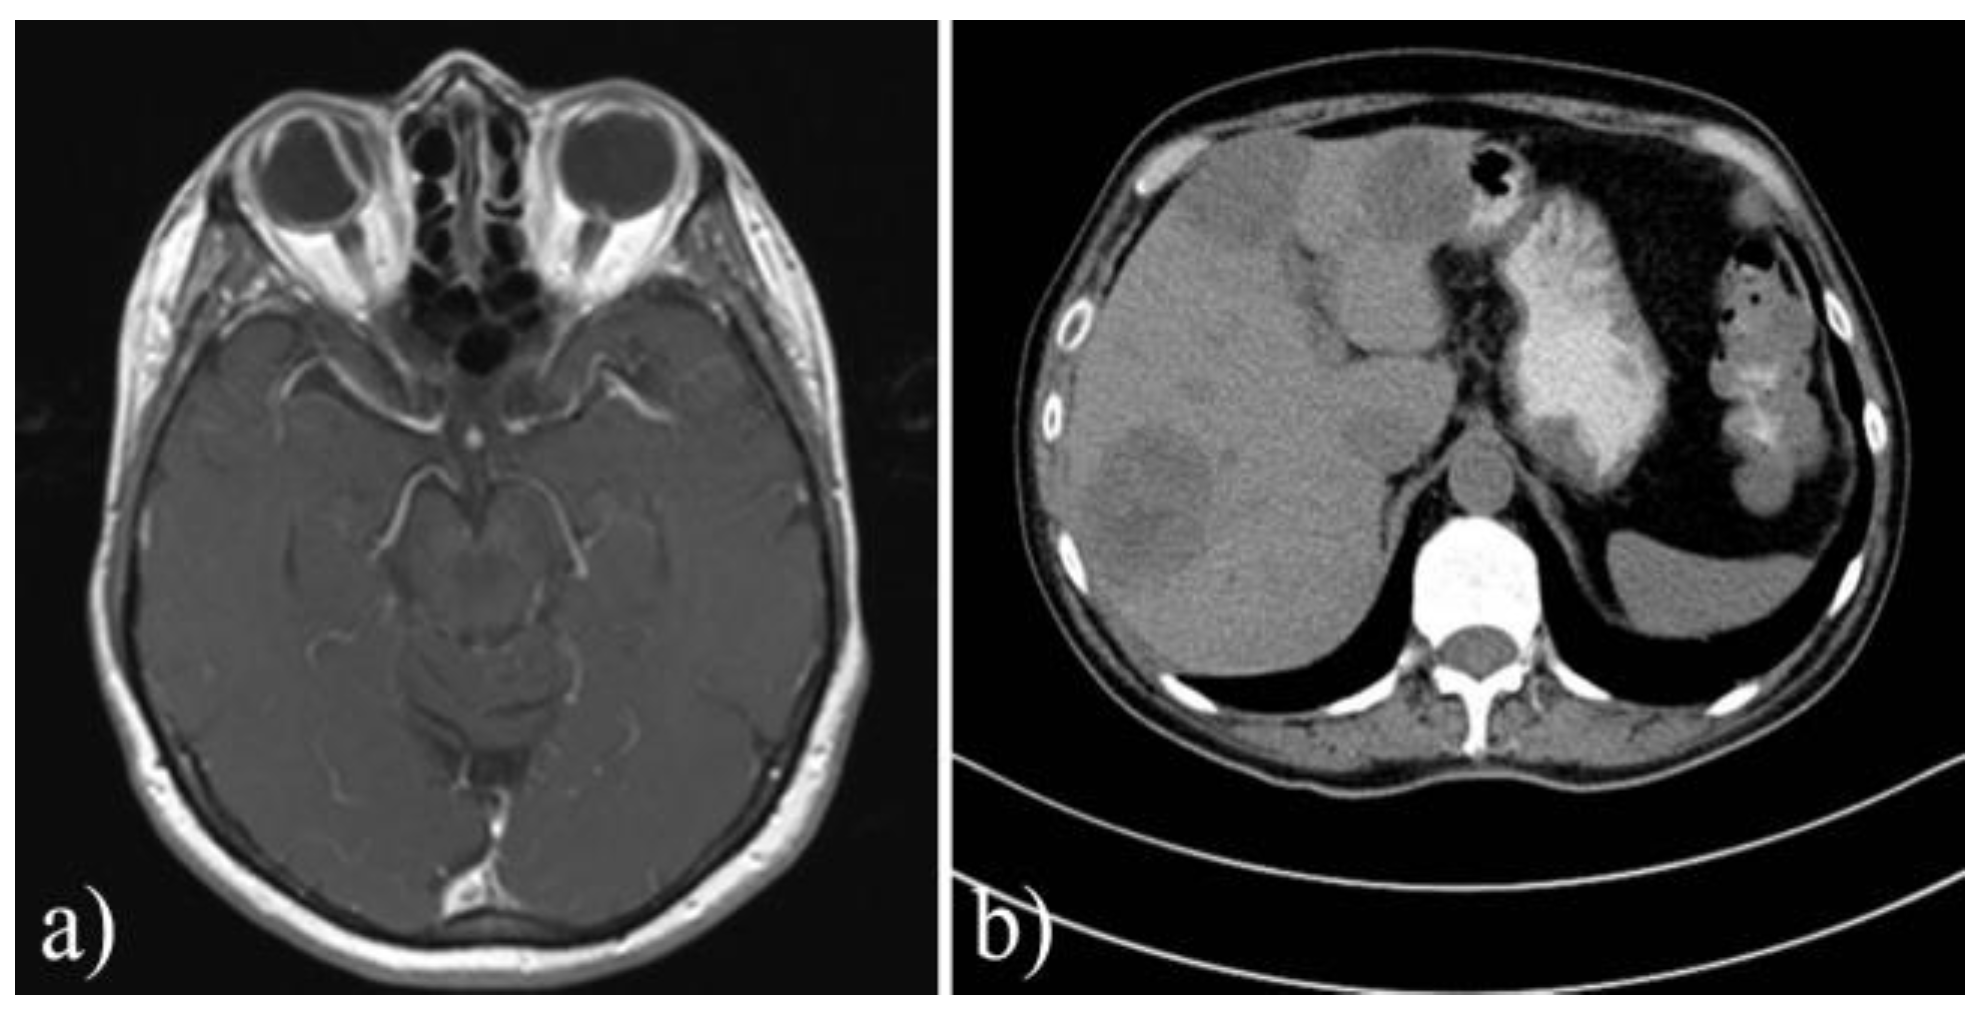

| CT/IRM for involved orbit | 10 (17.8%) | 2 (8.33%) | 8 (25%) | 0.1 |